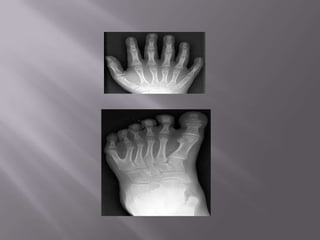

   Es toda desviación de

la mano y muñeca con

respecto al antebrazo

(mano bot).

   Ocurre con mayor

frecuencia en los pies.

   El niño nace con dedos de menos o están

ausentes amputaciones congénitas.

   La falta total de un dedo suele coincidir con la

ausencia de su metacarpiano o metatarsiano

   Dos o mas dedos

están unidos entre por

tejido blando.

   Mayor numero de

dedos. Metacarpiano

o Metatarsiano.